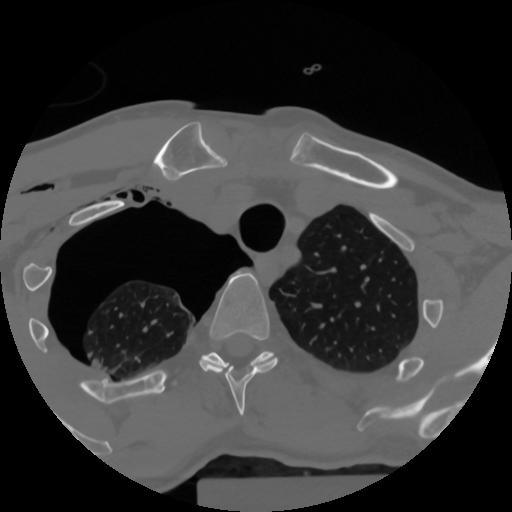

12 P.BLANDAS,,Vol,0.5,P.BLANDAS,,